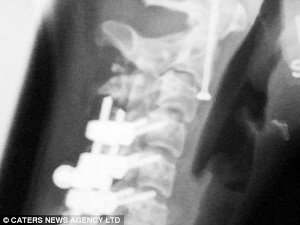

经过进一步的诊断,医生认为,如果不在卡特莉娜的大腿、脖子和背部插入金属材料以固定碎骨,她的脊柱损伤可能继续恶化,甚至危及生命。入院第二天,医生在其左腿植入一根长长的钛棒,从她的左半侧臀部一直插到左膝盖。然后,再用4根钛金属别针加以固定。

入院一周之后,风险更大的手术开始。医生切开了卡特莉娜的后背,然后并列插入6根水平方向的钛金属棒,用于支撑她断裂的脊柱。又过了一周,医生在她的脊柱顶端又插入一枚螺钉,用于支撑她因骨折而脆弱不堪的颈部。三次手术之后,医生在卡特莉娜的体内总共植入了11根钛棒以及数十根螺钉和别针,用于固定碎裂的骨头。